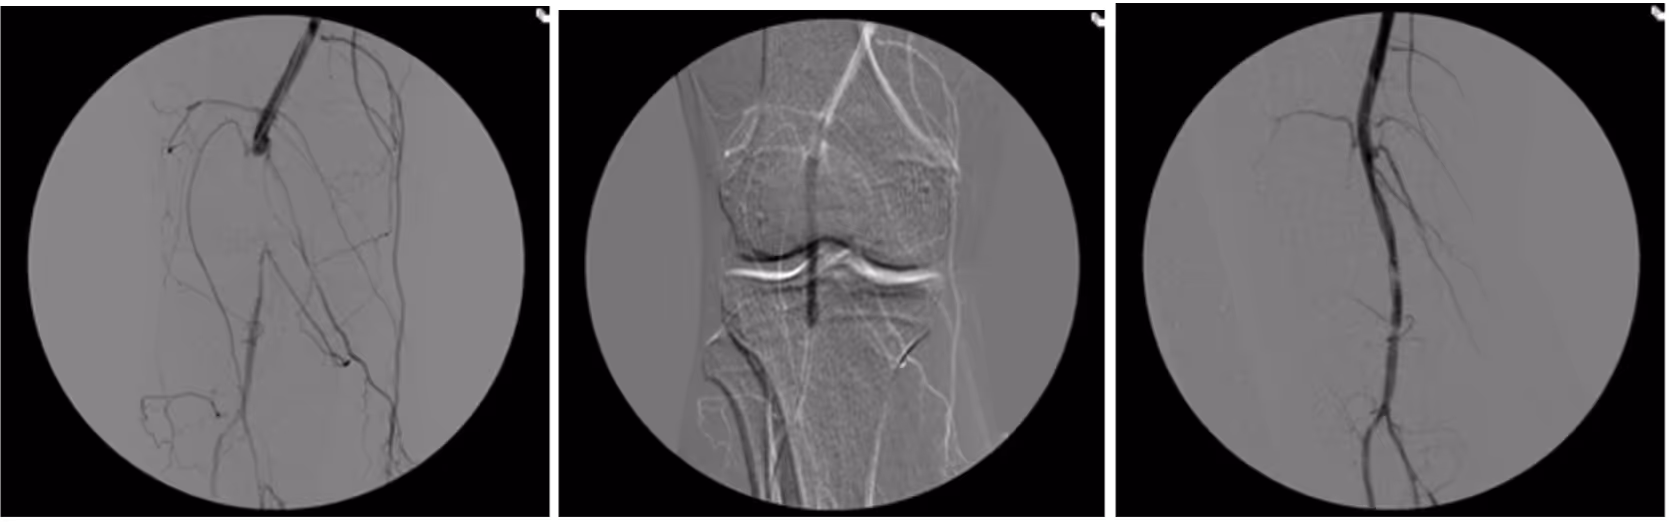

Many peripheral stenoses and occlusions are accessible by endovascular means. Among the endovascular procedures treatment of iliac and femoro-popliteal stenoses/occlusions are the most often used techniques. Thorough planing, proper use of endovascular tools and adherence to meticulous endovascular techniques are therefore of upmost importance for the success.